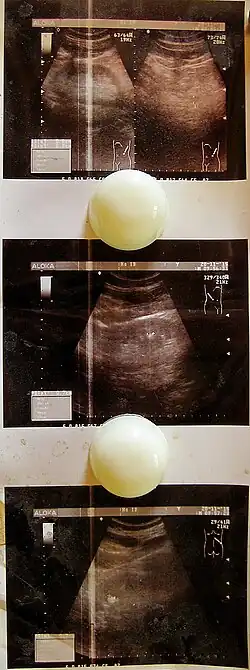

Эхопризнаки цистита на УЗИ

Установить диагноз острого цистита можно при наличии нескольких факторов:

Диагностика хронического цистита основывается на анамнестических данных, характерных симптомах заболевания, результатах макро- и микроскопии мочи, данных бактериологических исследований, цистоскопии (после стихания острого воспаления), функциональных исследований состояния нижних мочевых путей.

• УЗИ мочеполовых органов, позволяющее исключить сопутствующие заболевания;